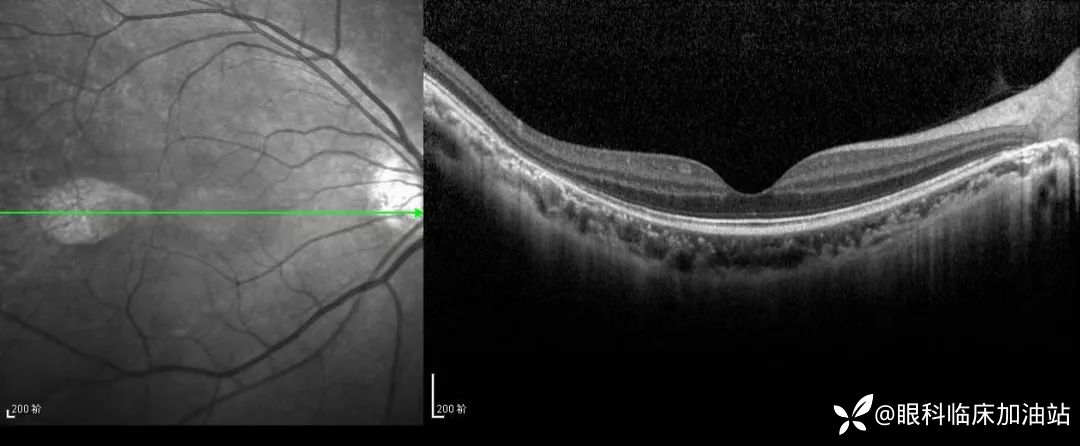

眼底照相

局部细节图

OCT图像

OCT:黄斑中心凹处未见明显异常,其颞侧节段样视网膜厚度变薄,RPE层及外核层及外层高反射条带缺失;其下脉络膜层反射增强。